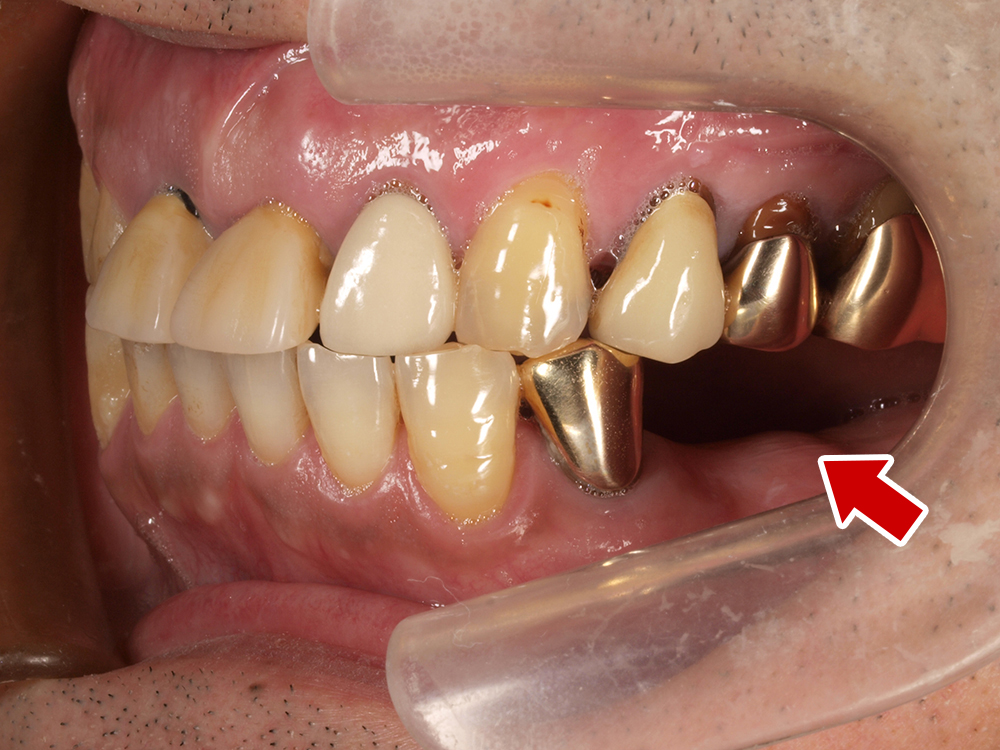

58歳 男性 歯科医療関係者紹介

- 主訴

- 右下を抜歯して噛めない

- 処置内容

- インプラント2本埋入

- 治療費用

- 約80万円(税込)

- 治療期間

-

8か月

仮歯完成まで5か月(この時点で噛めます)、+3か月で最終素材へ

- リスク

- 上部構造物、仮歯の破折、術後の腫れ(3日)、人工歯根脱落リスクがあります